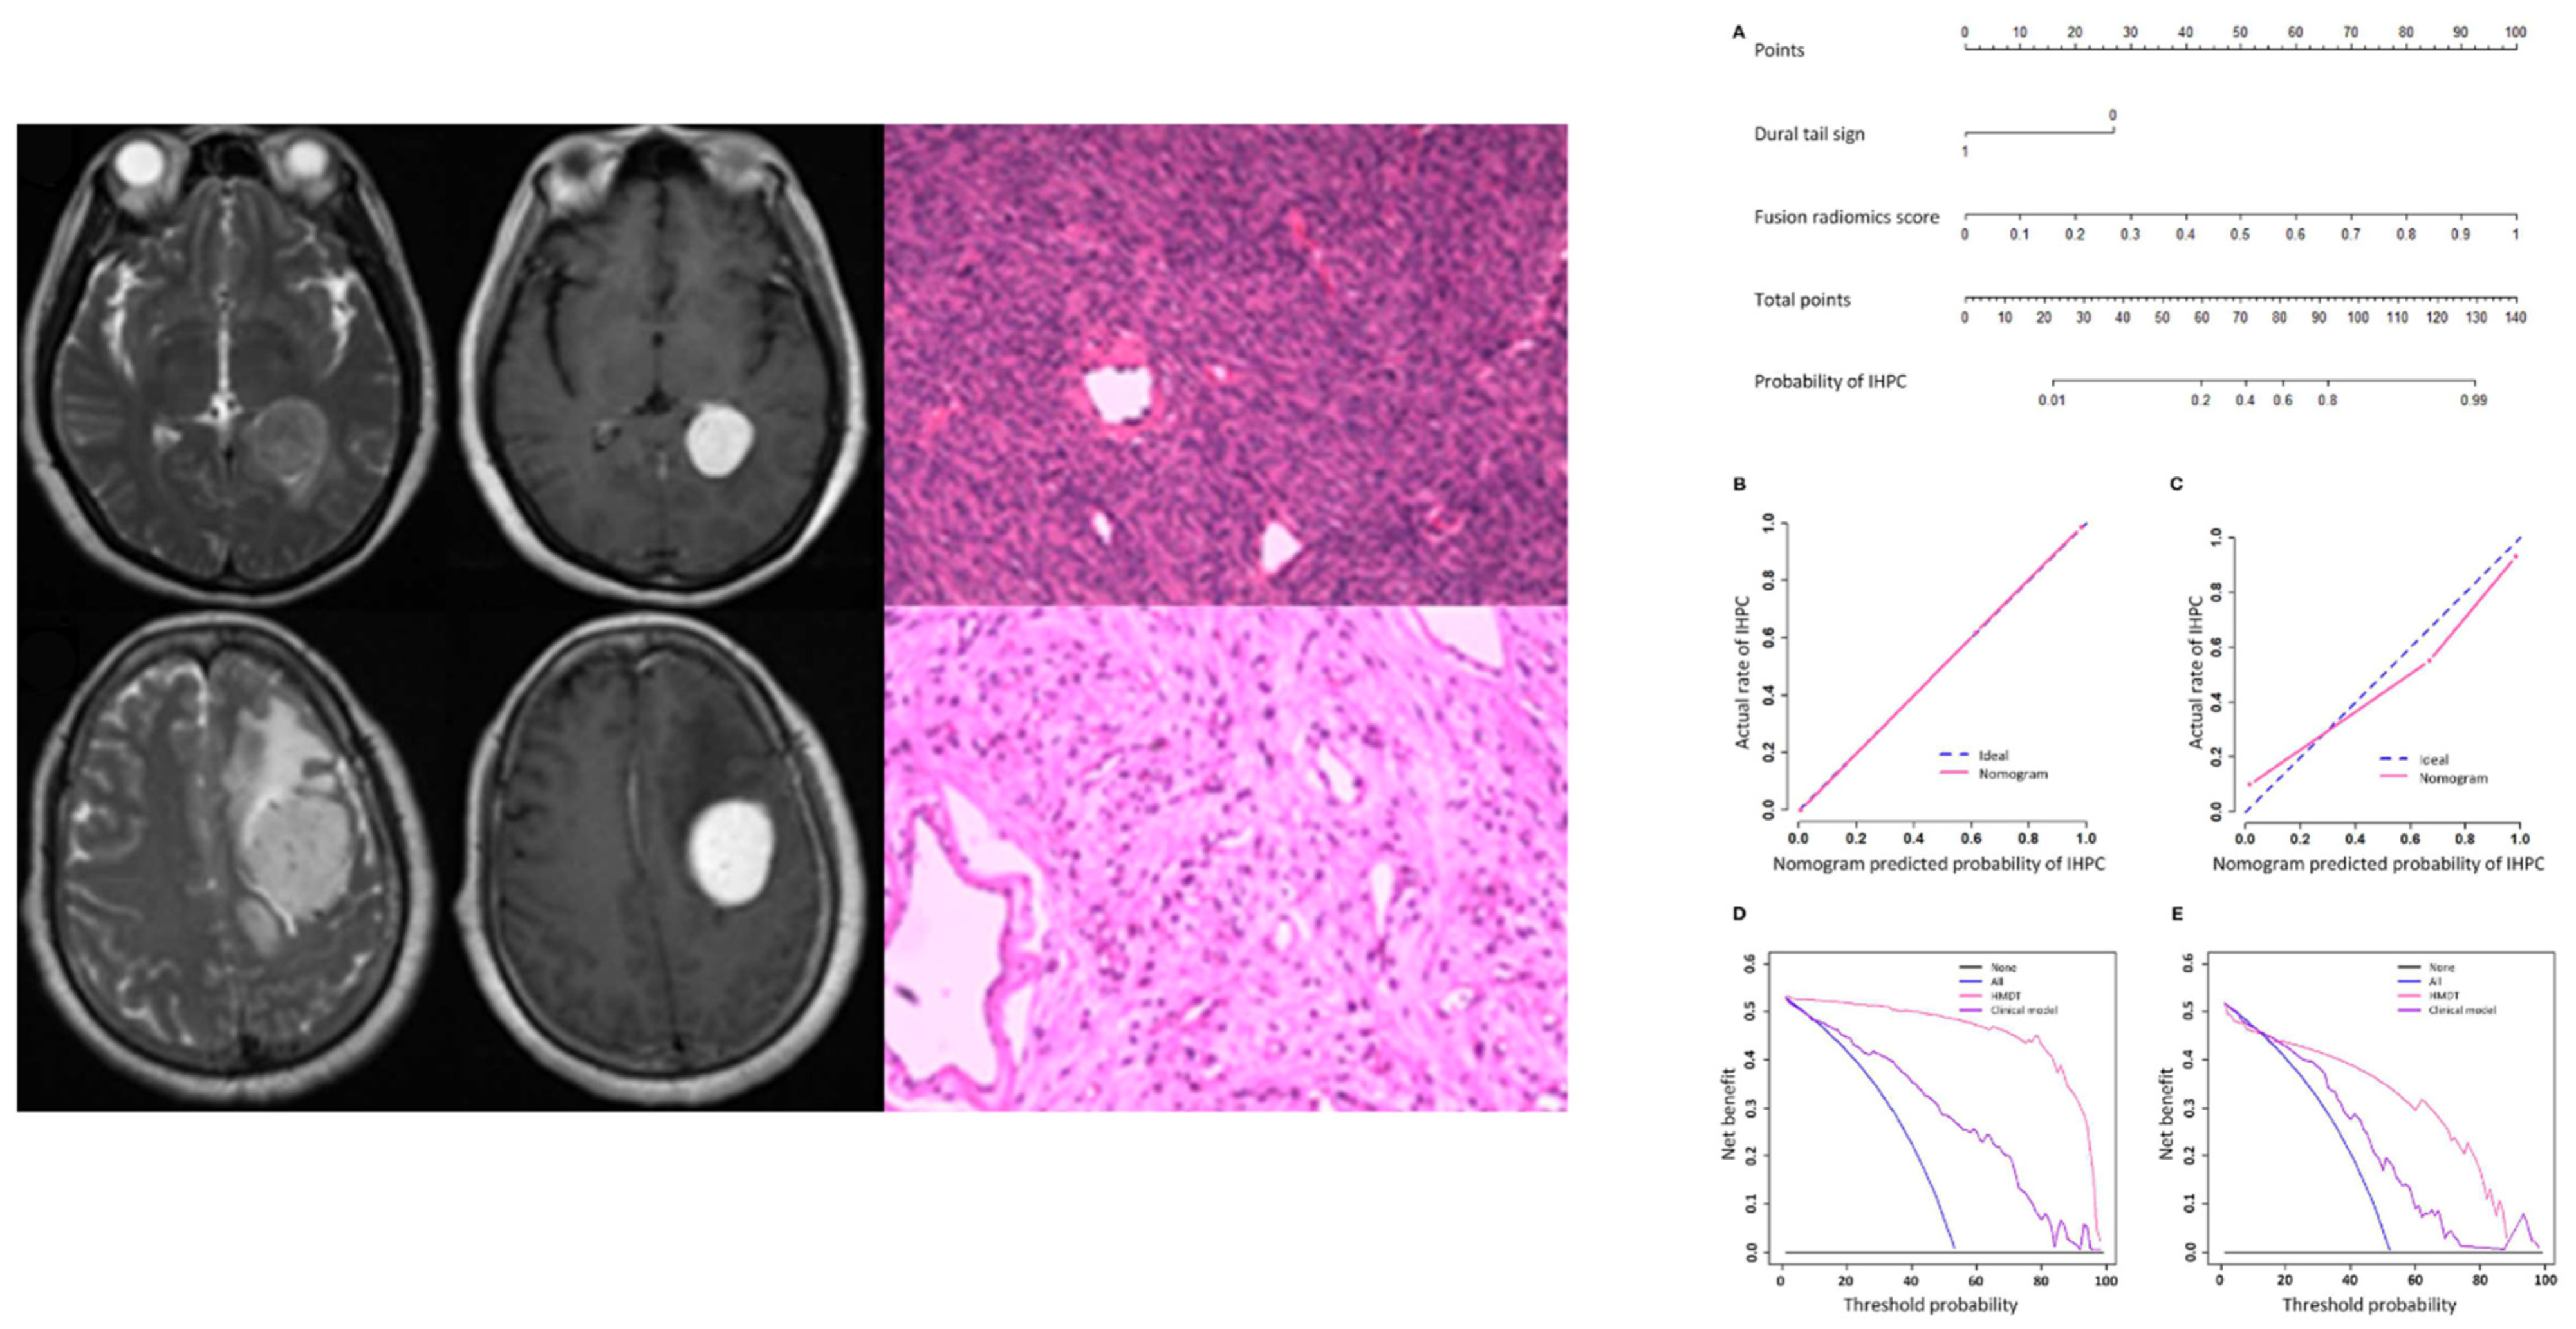

| Fan et al. [9] | 2022 | 220 | CE-T1, T2 | Characterization | Clinic-radiomic model | 3D | Differential diagnosis of intracranial hemangiopericytoma and angiomatous meningioma |

| Wei et al. [20] | 2020 | 292 | CE-T1, T2, T1 | Characterization | Clinic-radiological data and radiomics signature | 3D | Distinction of intracranial hemangiopericytoma from meningioma |